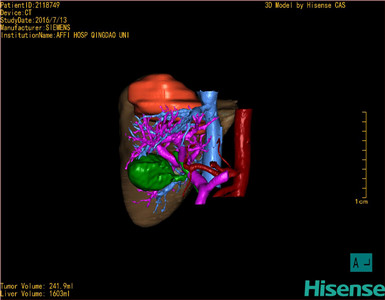

术前三维重建及手术方案设计:

将0.625mm双源薄层CT资料的静脉期和动脉期Dicom格式文件导入海信CAS系统。

通过调节窗宽窗位调整CT序号,对肿瘤,肝实质,胆囊,下腔静脉,肿瘤,肝动脉、门静脉及肝静脉等进行三维重建;系统自动计算肿瘤体积和肝脏体积。

模拟手术操作,自动计算切除肿瘤体积。肝脏体积为1603ml,肿瘤体积为241.9ml,肿瘤体积为肝脏体积的15.1%,通过比对70-80岁正常肝脏体积为1118.08±190.14ml,通过术前模拟手术,精准判断切除后剩余肝脏体积能耐受,避免肝衰竭发生。

术前手术方案的规划。

术前三维重建:

重建图片